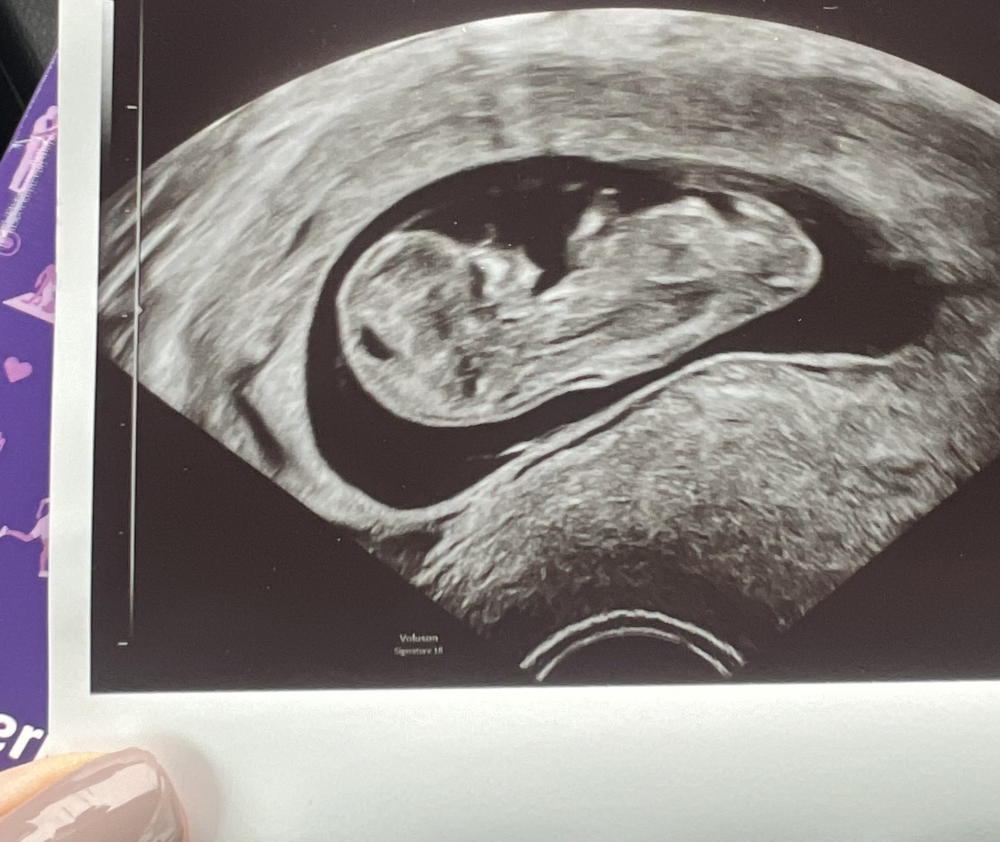

vllt habt ihr ja eine Vermutung nach was für einem Geschlecht die Ultraschallbilder aussehen. 🙂

Das erste Bild ist von 11+2 und das zweite Bild von12+3

Kann man da überhaupt etwas erkennen?